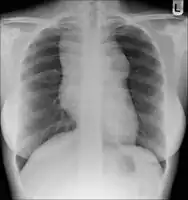

- Lymphadenopathy: the most common symptom of Hodgkin is the painless enlargement of one or more lymph nodes.[14] The nodes may also feel rubbery and swollen when examined. The nodes of the neck and shoulders (cervical and supraclavicular) are most frequently involved (80–90% of the time, on average).[14] The lymph nodes of the chest are often affected, and these may be noticed on a chest radiograph.[14]

After Hodgkin lymphoma is diagnosed, a person will be staged: that is, they will undergo a series of tests and procedures that will determine what areas of the body are affected. These procedures may include documentation of their histology, a physical examination, blood tests, chest X-ray radiographs, computed tomography (CT)/Positron emission tomography (PET)/magnetic resonance imaging (MRI) scans of the chest, abdomen and pelvis, and usually a bone marrow biopsy. Positron emission tomography (PET) scan is now used instead of the gallium scan for staging. On the PET scan, sites involved with lymphoma light up very brightly enabling accurate and reproducible imaging.[30] In the past, a lymphangiogram or surgical laparotomy (which involves opening the abdominal cavity and visually inspecting for tumors) were performed. Lymphangiograms or laparotomies are very rarely performed, having been supplanted by improvements in imaging with the CT scan and PET scan.